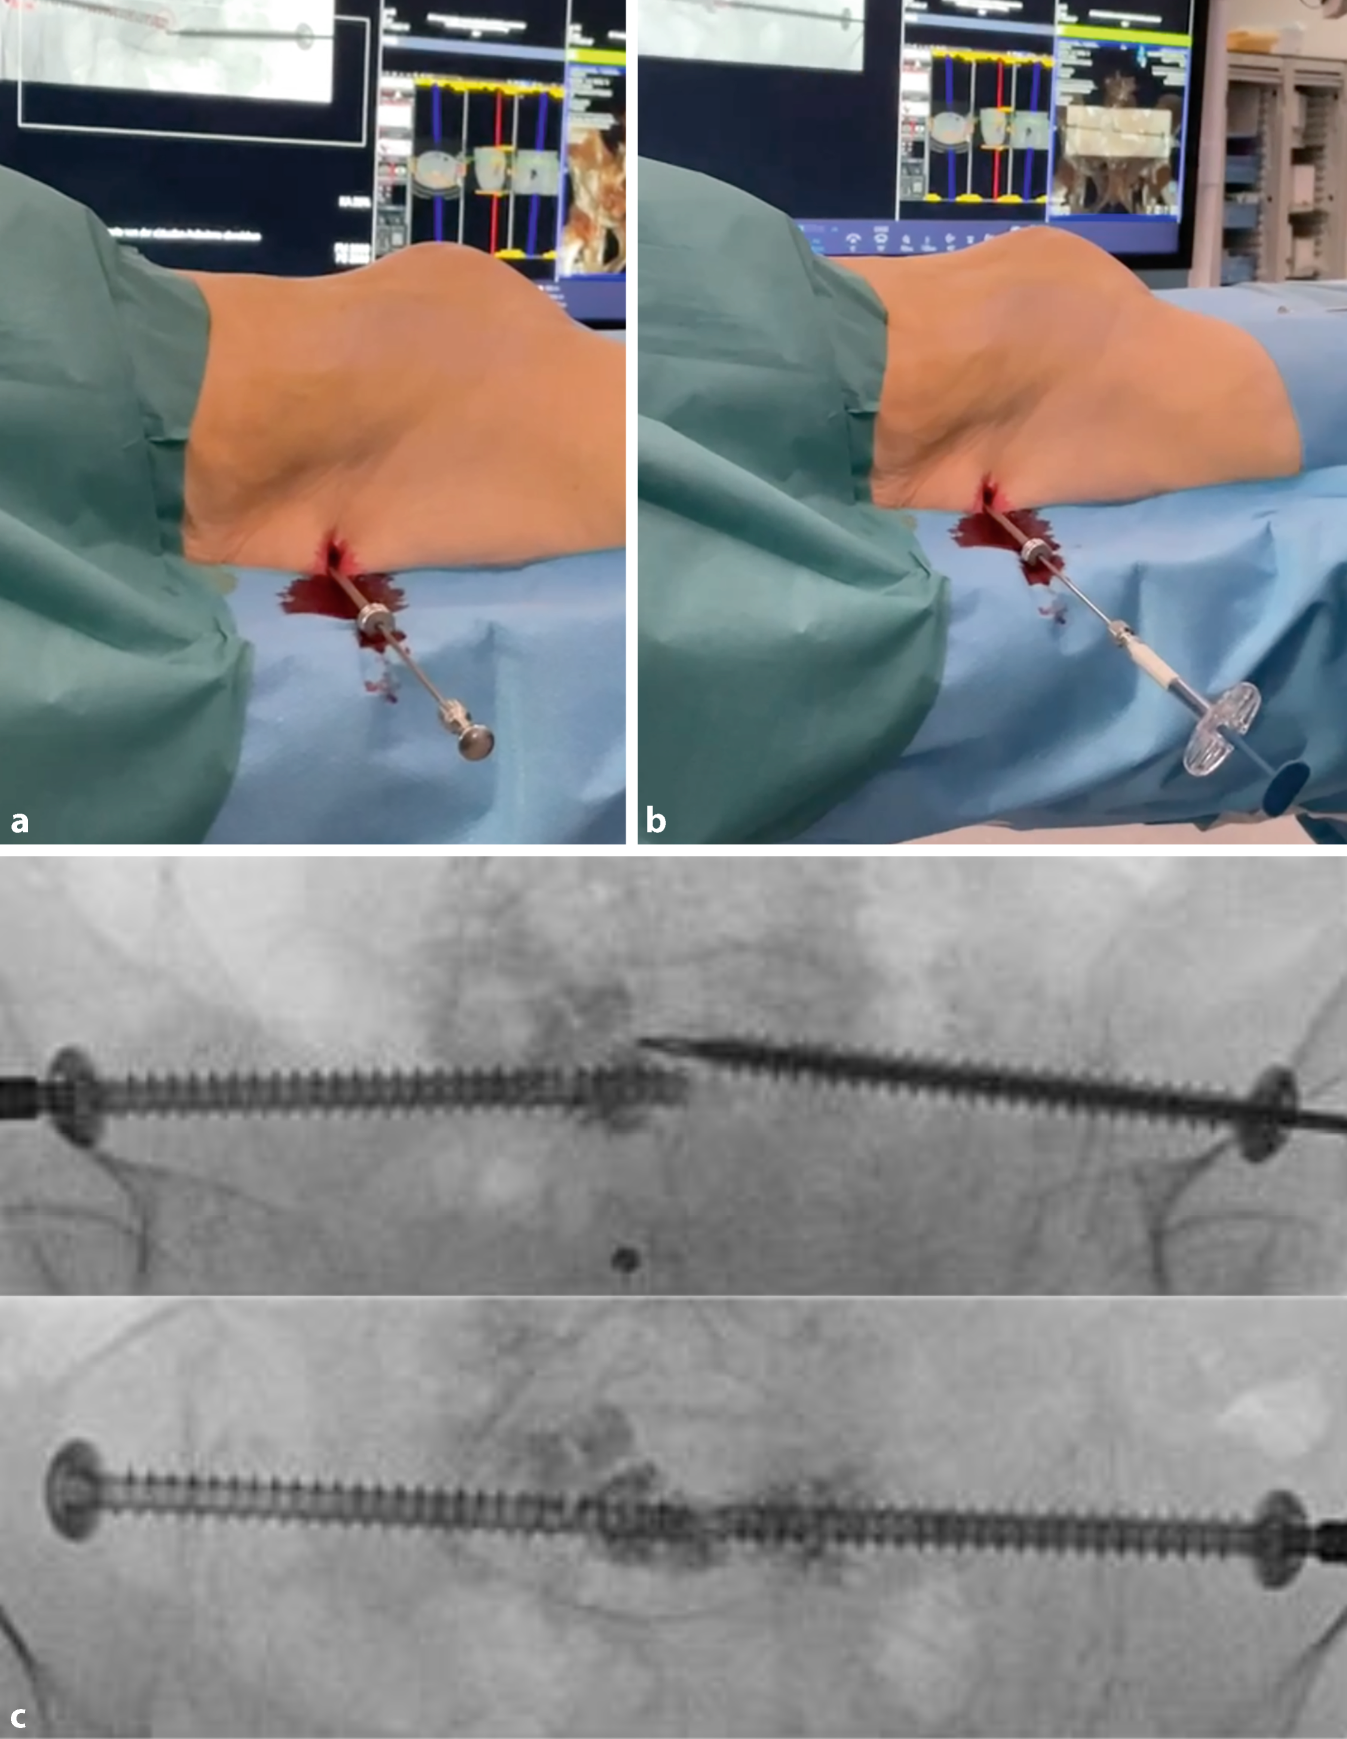

Fig. 6

Lateral fluoroscopic image with real-time projection of the planned guide-wire entry point (green cross), its direction (dotted line), and endpoint (red circle). The guidewire is positioned on the bone. Once correctly positioned, it is introduced into the bone via light mallet strikes until it penetrates three cortices. If the correct angle in the axial plane is achieved (usually 10–20°), the guidewire advances along the planned trajectory in the lateral view. The planned screw pathway is visible at all times on the fluoroscopic images, to allow for navigation and direct adjustment of the guidewire. To minimize the surgeon’s radiation exposure, the guidewire is held with a forceps

Fig. 7

The guidewire position is verified using the predefined personalized inlet and outlet angles (see appendix 2). While alternating between these personalized angles, the guidewire can be repositioned and driven into its final position with the drill. Key to this process is keeping in mind the vital landmark: the slightly S‑shaped anterior cortex of the S1 vertebral body. In uncertain scenarios, a higher dosage x‑ray may be acquired, or the contralateral side extrapolated for reference. Possible mismatch between diagnostic and intraoperative CT may result in an inaccurate planned screw pathway overlay; in such cases, the overlay can still provide an estimated guidewire pathway and end position. After final placement of the guidewire, its length is measured